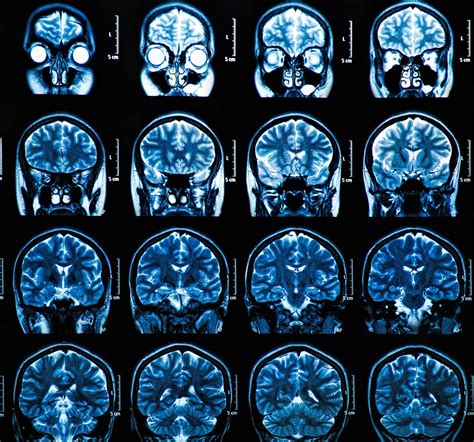

Computed Tomography (CT) scans use X-ray technology to create cross-sectional images of the brain. It is highly effective at identifying acute structural abnormalities. However, it is crucial to understand that a CT scan for concussion is primarily a safety screening tool, not a diagnostic test for the concussion itself.

Concussions are functional injuries—meaning they affect how the brain works—rather than structural ones that change the physical appearance of the brain tissue. Therefore, a patient can have a completely "normal" CT scan and still suffer from severe concussion symptoms, such as headaches, dizziness, and cognitive impairment. The scan exists to catch the "red flags" that require surgical or immediate neurological management.

Because the procedure is fast, it is the preferred method for assessing patients who are agitated, confused, or physically unstable. Once the images are captured, they are reconstructed by a computer to allow a radiologist to examine the brain for signs of intracranial hemorrhage or hematoma (blood collection).

When a doctor reviews a CT scan for concussion, they are looking specifically for evidence of high-risk injuries. A negative scan—meaning the scan shows no injury—is excellent news. It means the patient does not have an acute bleed or fracture requiring surgery. However, a negative scan does not rule out the diagnosis of a concussion. The concussion diagnosis is based on the patient's symptoms and clinical assessment rather than imaging.